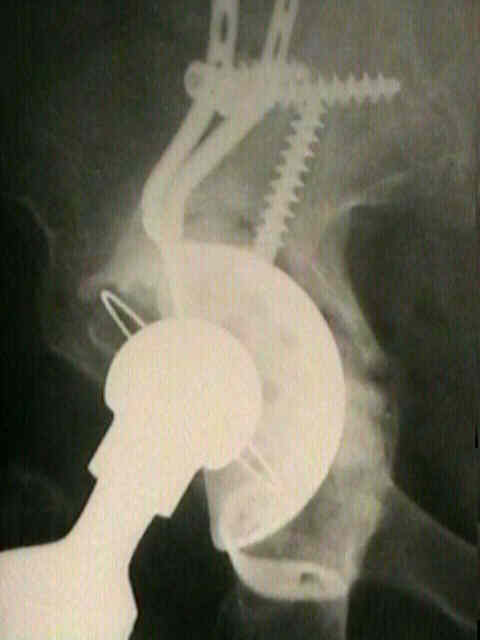

- treatment may require insertion of posterior column reconstruction plate and a gap cup

- w/ segmental deficiency, consider use of an antiprotrusio cage augmented w/ particulate bone graft or a single structural bone graft;

- Burch-Schneider antiprotrusio cage was used to reconstruct 13 hips, and the socket remained stable in all thirteen;